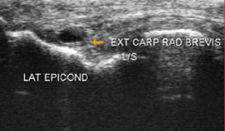

Tennis elbow involves inflammation and degeneration of the Extensor Carpi Radialis Brevis (ECRB) tendon where it inserts into the elbow (lateral epicondyle). This muscle is a pure wrist extensor and so the demand placed upon it during forceful and repeated wrist extension is high. Add to that, age (weakening the tendons and the muscles) and then activity (bricklaying, typing) and it is not surprising that the tendons of this muscle can tear.

Tennis Elbow requires a thorough physical examination by an experienced hand therapist, once the diagnosis is complete, a treatment plan is prepared to get you back to the things you love. Action Rehab hand therapists will ask, where the pain is, what sort of pain is it (shooting? burning?). Action Rehab hand therapists will assess your strength, your motion and your occupations to see what the symptoms and most importantly what the cause may be. In most cases, your medical history and physical exam will be enough for us to make a diagnosis. However, if an MRI, ultrasound or X-Ray is required our Physiotherapists, and Occupational Therapists can read and interpret the results.